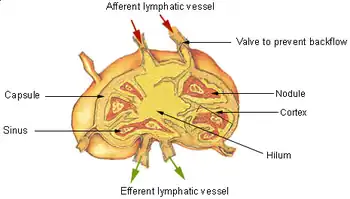

Diagram showing major parts of a lymph node | |

A lymph node, or lymph gland,[1] is a kidney-shaped organ of the lymphatic system and the adaptive immune system. A large number of lymph nodes are linked throughout the body by the lymphatic vessels. They are major sites of lymphocytes that include B and T cells. Lymph nodes are important for the proper functioning of the immune system, acting as filters for foreign particles including cancer cells, but have no detoxification function.

In the lymphatic system, a lymph node is a secondary lymphoid organ. A lymph node is enclosed in a fibrous capsule and is made up of an outer cortex and an inner medulla.

Each lymph node is surrounded by a fibrous capsule (made of collagenous connective tissue),[3] which extends inside a lymph node to form trabeculae.[4] The substance of a lymph node is divided into the outer cortex and the inner medulla.[4] These are rich with cells.[5] The hilum is an indent on the concave surface of the lymph node where lymphatic vessels leave and blood vessels enter and leave.[5]

Lymph enters the convex side of a lymph node through multiple afferent lymphatic vessels, and from there, it flows into a series of sinuses. Upon entering the lymph node, lymph first passes into a space beneath the capsule known as the subcapsular sinus, then moves into the cortical sinuses. After traversing the cortex, lymph collects in the medullary sinuses. Finally, all of these sinuses drain into the efferent lymphatic vessels, which carry the lymph away from the node, exiting at the hilum on the concave side.

Subdivisions

A lymph node is divided into compartments called nodules (or lobules), each consisting of a region of cortex with combined follicle B cells, a paracortex of T cells, and a part of the nodule in the medulla.[17] The substance of a lymph node is divided into the outer cortex and the inner medulla.[4] The cortex of a lymph node is the outer portion of the node, underneath the capsule and the subcapsular sinus.[17] It has an outer part and a deeper part known as the paracortex.[17] The outer cortex consists of groups of mainly inactivated B cells called follicles.[5] When activated, these may develop into what is called a germinal center.[5] The deeper paracortex mainly consists of the T cells.[5] Here the T-cells mainly interact with dendritic cells, and the reticular network is dense.[18]

The medulla contains large blood vessels, sinuses and medullary cords that contain antibody-secreting plasma cells. There are fewer cells in the medulla.[5]

The medullary cords are cords of lymphatic tissue, and include plasma cells, macrophages, and B cells.